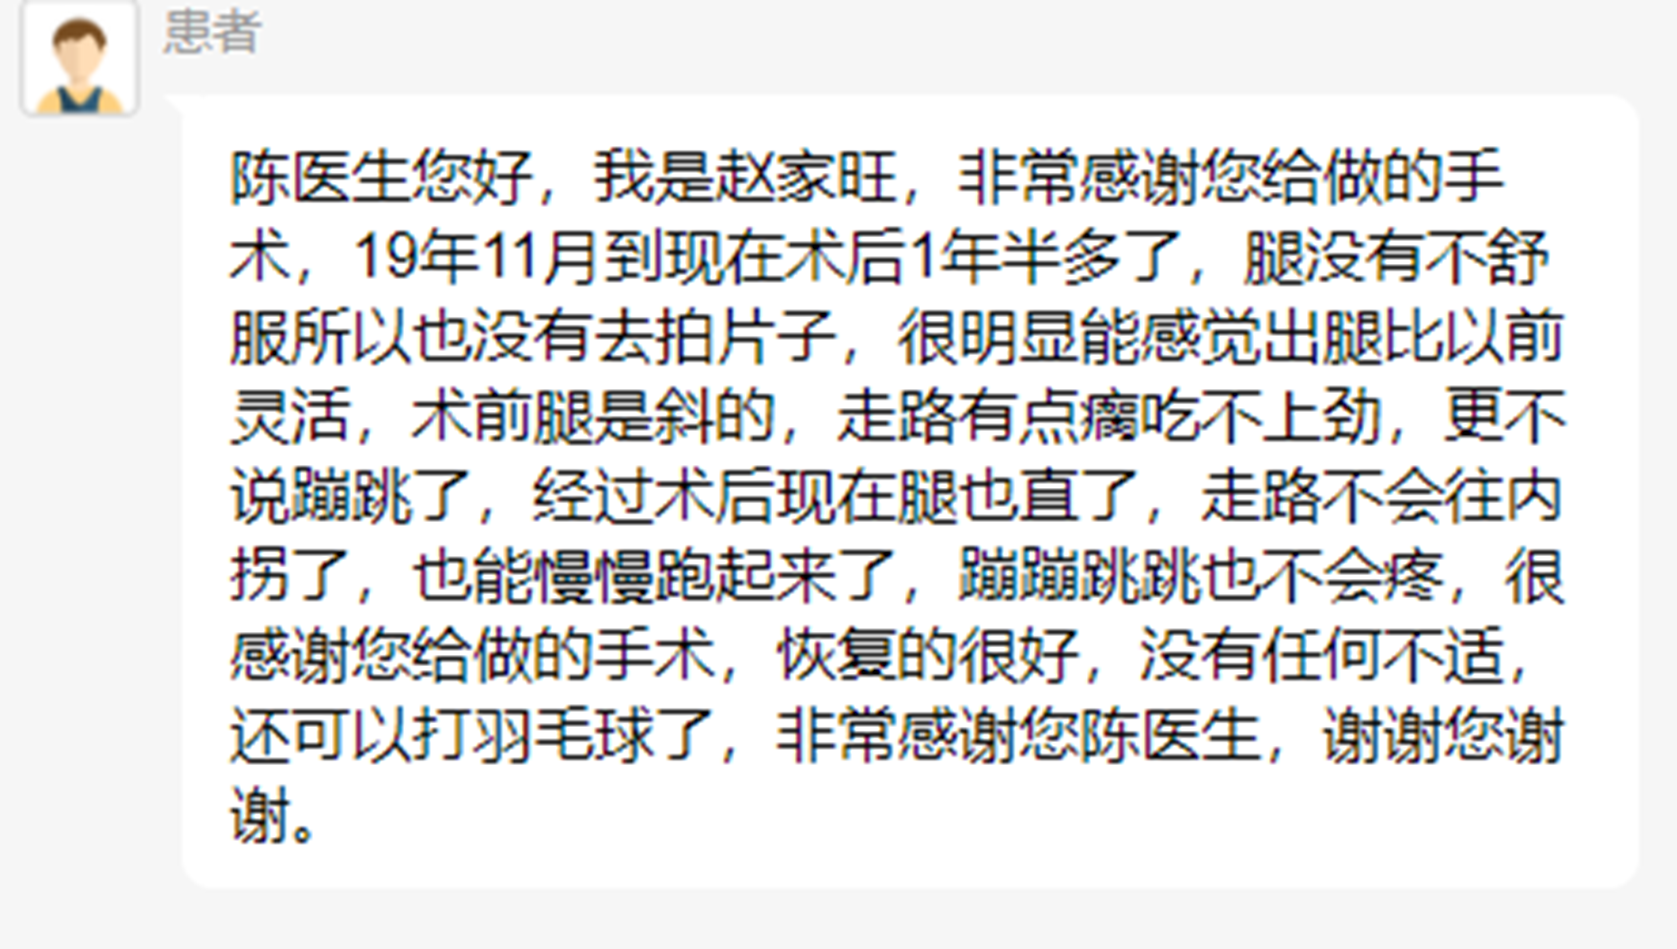

截骨矫正后,患者症状缓解,可以正常跑跳活动了。

患者完全恢复